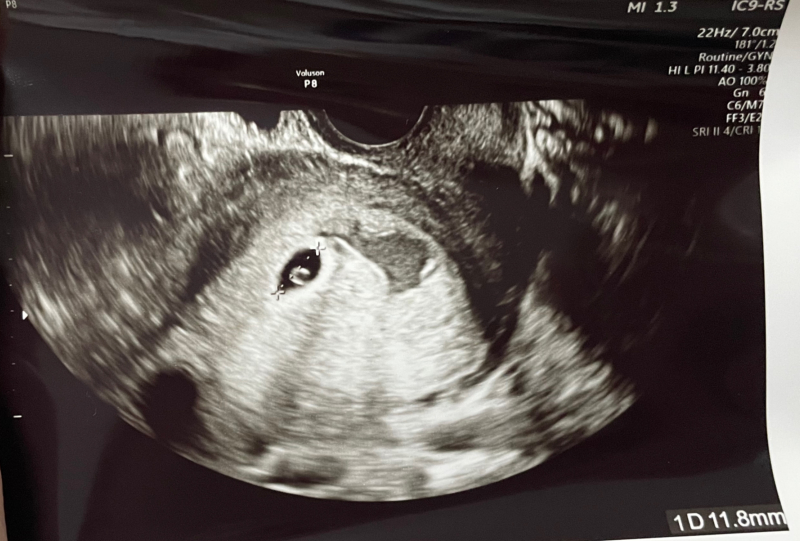

先日、初診受診したところ5w3dとのことで

胎嚢、卵黄嚢確認できました。

ただ、子宮の近くに血の塊があるそうで

絨毛膜下血腫と言われました。

今胎嚢は11.8mm、血腫はおそらく2cmくらいと言われました。

胎嚢よりも大きいこともとても不安です…